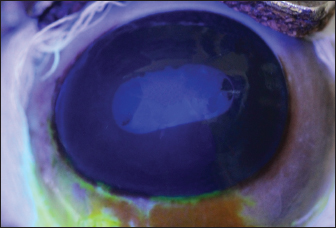

The study was approved by the Research of Committee of the Federal University of Rio Grande do Sul. The eyes were donated by a local slaughterhouse. Twenty eyeballs from 10 Brangus breed male bovines aged 24 months were studied. Enucleation was made immediately after slaughtering, and the eyes were labeled and stored in a moist chamber until analysis under a specular microscope. All ocular bulbs underwent an ophthalmic examination which included biomicroscopy with a slit lamp (Kowa SL-15, Nagoya, Aichi, Japan) (Fig. 1) and a fluorescein test (1% sodium fluorescein, Allergan, Sao Paulo, Brazil) (Fig. 2). Only healthy eyes were selected. Only eyes with transparent corneas and eyes with a negative fluorescein test were included in the study. All analyses were carried out within 4 hours after slaughter. For endothelial evaluation, a contact specular microscope (Celmax, Medical Service, Sao Carlos, Brazil) was used. All evaluations were carried out by the same examiner. After being removed from the wet chamber, the eyes were placed on a support adapted to the contact specular microscope and lubricated with ophthalmic eye drops (Lacri, carboxymethylcellulose). The objective lens of the specular microscope was positioned in the central region of the cornea, at a 90° angle between the evaluated structure and the device (Figs. 3 and 4). From each cornea, we obtained one micrograph, and 30 endothelial cells were analyzed in each image. Cell density was calculated using software coupled to the specular microscope (Celmax® specular microscope). Endothelial morphology was obtained through manual assessment of the number of sides of each cell. The values obtained were the means of each identified parameter.

Fig. 1. Slit lamp examination of a bovine eye.

Fig. 2. Bovine eye after fluorescein staining. It is observed that the dye did not adhere to the cornea.